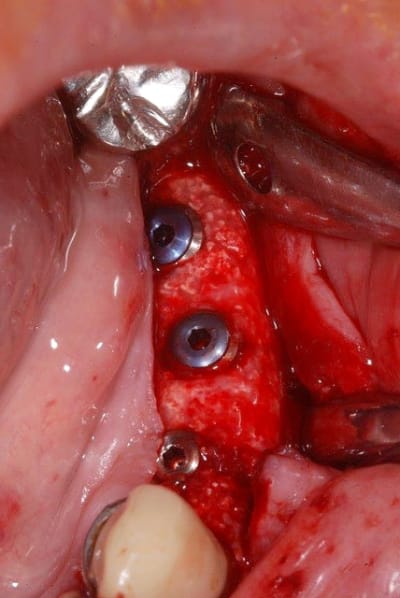

voici la nouvelle ligne muco-gingivale de la patiente.

photo 1 :ancienne lmg (quasiment sur la crête osseuse)

photo 2 : nouvelle lmg

c'est un peu long à cicatriser, on verra dans 1 à 2 mois